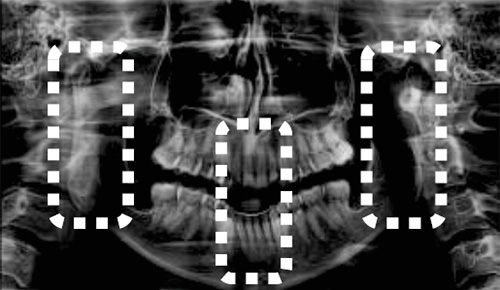

CT撮影では、症例に応じてFOV(Field of View:撮影範囲)を設定します。「Green X 12」では7種類のFOVから診断目的に合わせ最適な選択ができます。

マルチFOVセレクション